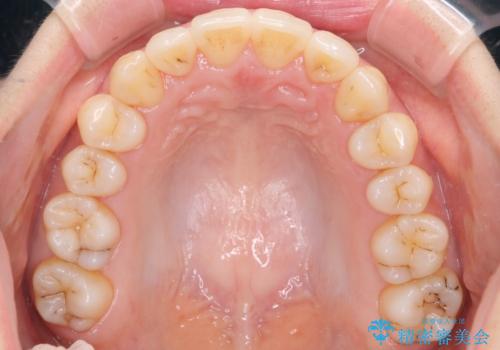

前歯が前後反対にかんでいる インビザラインによる目立たない矯正

歯と歯の間をわずかに削り、ガタガタを改善しました。

目立たずに矯正を終えることができて、喜んでいただけました。